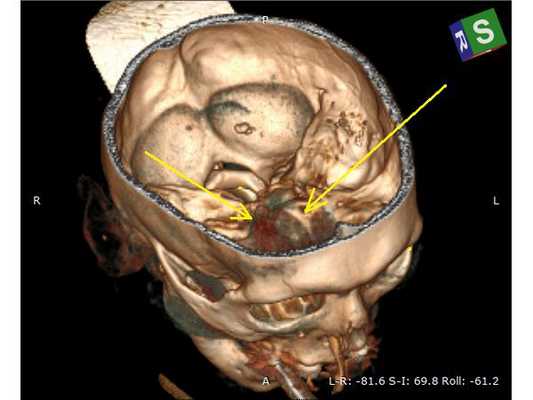

- Оскольчатый вдавленный перелом правой теменной кости.

- Скелетирована кость (надкостница отделена от кости). Гемостаз (остановка кровотечения) по ходу доступа. Визуализирован импрессионный перелом правой теменной кости.

- Краниотомом наложено фрезевое отверстие ниже вдавленного перелома и выпилен костный лоскут 5,0 х 6,0 см с захватом имеющегося импрессионного перелома. Костный лоскут временно удалён.

- Выполнена репозиция вдавленных фрагментов.